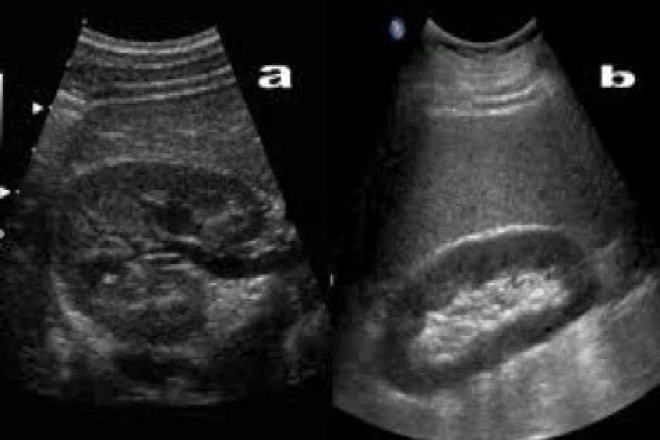

Enfermedad de Gaucher: Hallazgos por Ultrasonido en el bazo

Me resulto un tanto complicado hallar algún artículo que se relacionara a patología de bazo interpretada por medio de ultrasonido y este fue uno de los pocos que pude encontrar. La enfermedad de Gaucher no es muy conocida en el ámbito de la medicina general